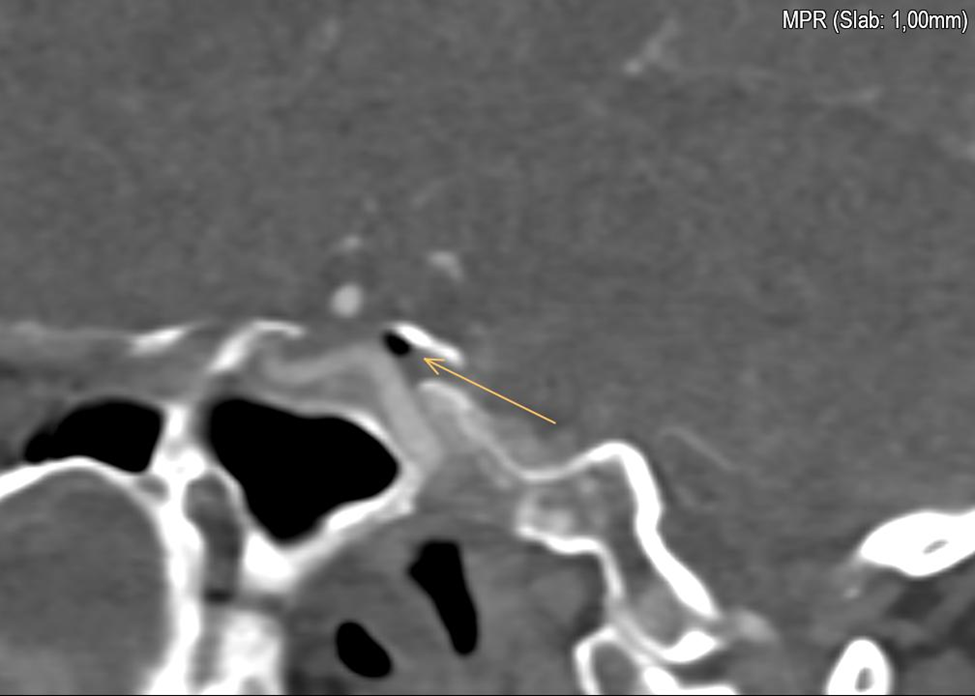

Neurovascular Assessment: An angiographic CT of the skull conducted during the neurological evaluation revealed the presence of air emboli in the cavernous sinus. Notably, echocardiographic assessment ruled out the presence of a patent foramen ovale (PFO), leaving the etiology of the air embolism due to several mechanisms unclear.

Primarily, they include a patent foramen ovale, the presence of right or left intrapulmonary shunts, and the forcing of air through the pulmonary filter. According to the literature on venous embolism, our case suggests that air likely migrated from the arm, passing through the right subclavian vein and entering the internal jugular vein on a cranial path. Once in the internal jugular vein, the air travels through the inferior petrosal sinus, ultimately reaching the cavernous sinus. Patients experiencing gas embolism may not exhibit symptoms; however, they can present with headache, nausea, vomiting, dizziness, or seizures. As the literature indicates, the etiology of these symptoms remains poorly understood.

Figure 1